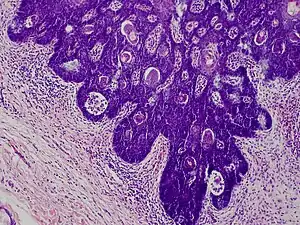

Folliculosebaceous cystic hamartoma abbreviated as (FSCH) is a rare cutaneous hamartoma consisting of dilated folliculosebaceous units invested in mesenchymal elements.[1]: 676 it typically affects adults, have a predilection for the central face or scalp, with less than 1.5 cm dimension.[2] Clinically, the lesions are asymptomatic, rubbery to firm in consistency, and usually occur on or above the neck in (> 90%) of cases, Histopathologically, FSCH shares several similar features to sebaceous trichofolliculoma, but it is usually possible to differentiate these two tumors.[3]

Dermatoscopy - folliculosebaceous cystic hamartoma, a)exophytic lesion, b)mature sebaceous lobules, c) stroma is prominent, with fibrillar bundles of collagen